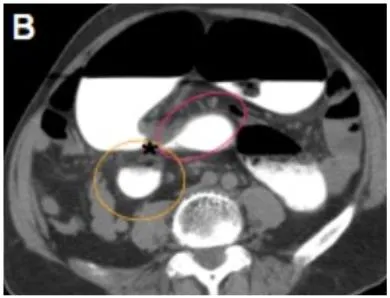

Whirl pattern, caused by the dilated sigmoid colon around its mesocolon & vessels

Bird-beak appearance of the afferent and efferent colonic segments

Large gas-filled loop lacking haustra, forming closed-loop obstruction

Whirl sign

Bird beak sign